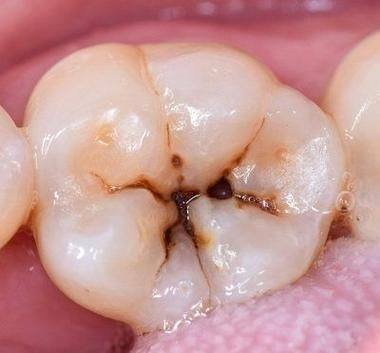

本文围绕龋齿从发生到烂完的时间展开,指出其受龋齿严重程度、口腔卫生、饮食习惯、治疗及时性等因素影响,时间从几个月到几年不等。为延缓或阻止龋齿进展,要保持良好口腔卫生、做好饮食管理、定期检查、及时治疗。文中还举例说明不同情况的龋齿发展差异,呼吁大家行动起来保护牙齿,远离龋齿困扰。